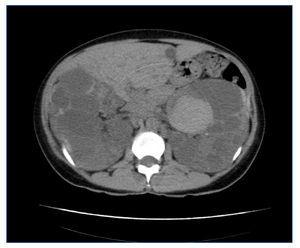

Figura 5. Corte axial de TC del caso 1 en el que se observan riñones muy aumentados de tamaño, con múltiples quistes con signos intraquísticos de hemorragia-hematoma (VRT = 2.877 ml).